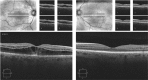

Spectral domain optical coherence tomography features in niacin maculopathy